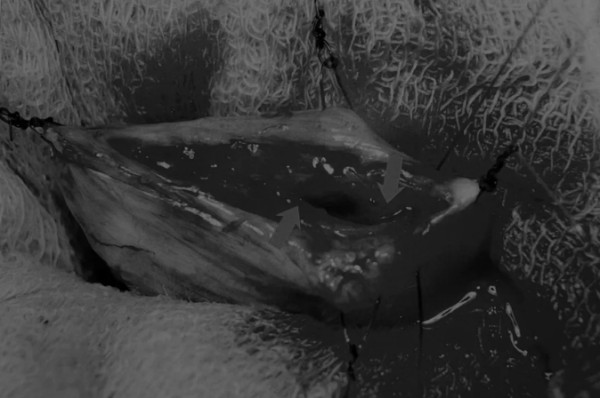

手术方法 在中线开腹手术后,确定膀胱,将其取出并隔离(图1)。为了使膀胱持续暴露,可在膀胱中线两侧各放置一根固定缝线(图2)。 在切开膀胱前,应用膀胱穿刺的方法获取尿液样本进行微生物培养。 图2 在手术过程中,还需要另外两根固定缝线来保持膀胱切开术的膀胱边缘处于暴露状态 在牵引缝线之间选择血管扩张较差的区域用手术刀切开膀胱壁(图3)。在牵引缝合线之间用手术刀在血管不良的区域做切口。切开膀胱壁后,膀胱内的手术可按手术方案实施,例如取出结石(图4)。 图3 避开主要的膀胱血管,做一个尽可能小的切口 切口可以在膀胱背侧或腹侧进行,避免对大血管的损伤。 图4 这张图显示了从膀胱中取出的大量结石 完成膀胱内冲洗后,应通过导尿管反向冲洗膀胱;砂样结石和血块会被冲到切口表面(图5) 图5 通过导尿管注入无菌生理盐水反向冲洗,可以去除微小的结石(箭头)和夹杂在膀胱黏膜皱褶中的砂样结石,以及可能在手术中形成的血块 膀胱创面采用单丝合成可吸收缝线缝合,采用外科医生习惯的缝合方式,但注意不要刺穿黏膜层(图6、图7)。 图6 使用简单的连续缝合。尽量不要用针刺穿黏膜层(箭头),以免缝线与尿液接触 图7 缝线应带入足够的切口两侧的膀胱组织,以确保在膀胱充盈时,没有伤口裂开 图8 这张图显示了通过导尿管注射的盐水,在缝合的切口处没有液体渗漏 关膀胱后,将无菌盐水注入膀胱腔内,检查是否有渗漏(图8)。 膀胱切开术闭合创口后,冲洗腹腔,以清除可能进入腹腔中的任何尿液、沙样结石或血凝块。 然后膀胱上覆盖小片的网膜,开腹手术伤口以通常的方式闭合。 手术视频 长按识别二维码观看视频